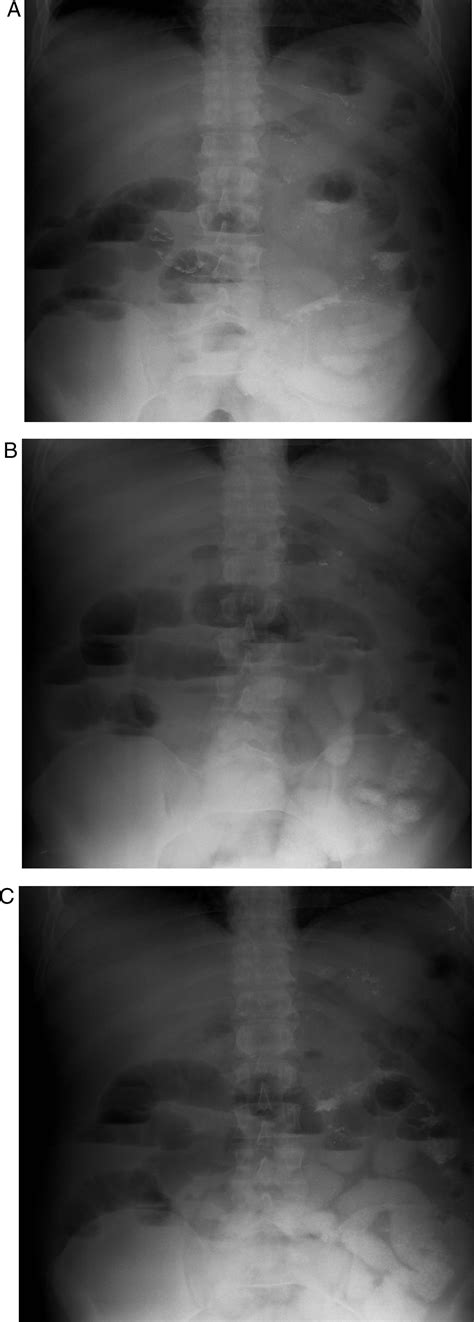

Estudio del Tubo Digestivo Alto Post-Gastrectomía Vertical en Manga (GSV)

En la gastrectomía vertical en manga, el estudio se centra en la evaluación del remanente gástrico tubular y la línea de sutura. Se busca detectar posibles filtraciones y evaluar el vaciamiento.

- Hallazgos radiológicos normales: El estómago se observa tubular, largo y delgado, sin evidencia de fugas ni torsión. Se muestra adecuado vaciamiento gástrico y paso del contraste hacia el duodeno e intestino delgado.

- Complicaciones: La filtración del medio de contraste puede ocurrir a nivel de la línea de sutura en la curvatura mayor, siendo la porción cefálica de esta línea de sutura un sitio frecuente. Se evalúa la presencia de colecciones líquidas adyacentes a la línea de sutura.